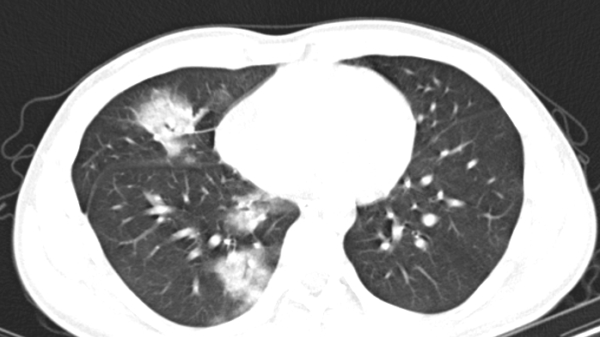

![]() |

| Ảnh minh họa |